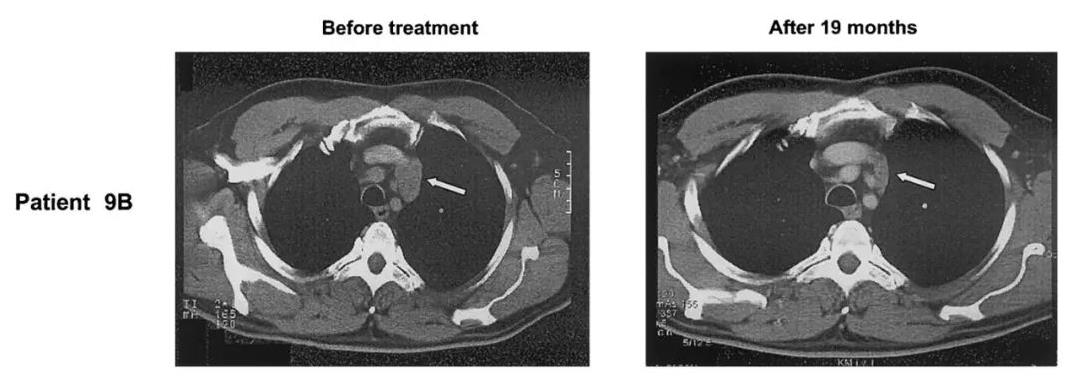

值得一提的是,其中1例达到部分缓解(PR)的患者(患者9B),既往曾接受过高剂量化疗,但病情仍然复发。入组后,经过3个周期的帕米膦酸盐/IL-2治疗后,CT扫描显示,大多数淋巴结没有明显变化,仅有1个淋巴结增大。该淋巴结的活检显示主要为纤维化,仅剩下少量淋巴瘤细胞。此后,肿瘤质量稳步下降,经过19个月的治疗,最终达到部分缓解(PR)(详见下图)。

图2 该患者治疗前后,CT图像对比

▲图源“Blood”,版权归原作者所有,如无意中侵犯了知识产权,请联系我们删除

注:CT扫描显示,该患者皮肤转移和纵隔淋巴结消退(箭头)。